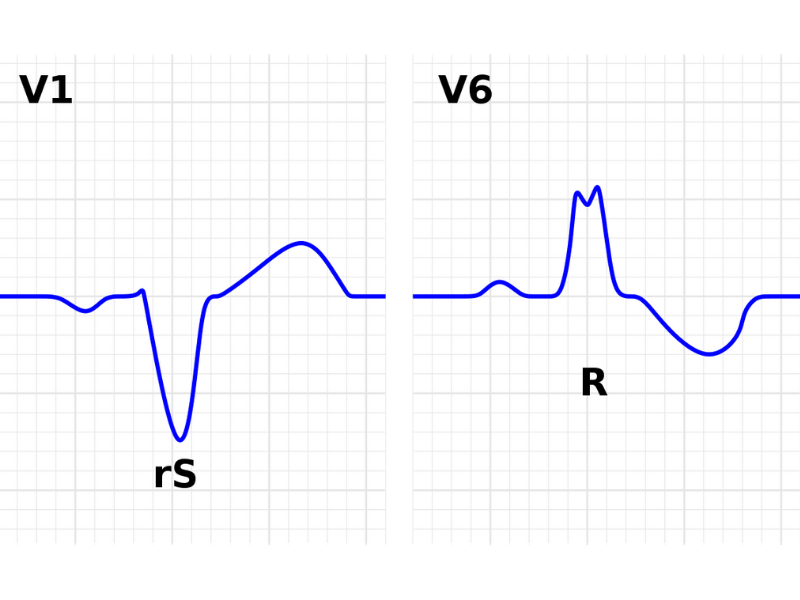

7) Bloqueios de ramos e divisionais

Uma das últimas etapas na descrição e interpretação do ECG é a avaliação da presença de bloqueios de ramo, direito ou esquerdo, e/ou de seus divisionais, como o bloqueio divisional antero-superior ou póstero-inferior.

Mas voltando à definição, o bloqueio de ramo ocorre quando a duração do complexo QRS é maior ou igual a 120 ms e classificado quanto ao ramo acometido, o direito ou esquerdo. Já os bloqueios divisionais, são descritos com QRS com duração menor que 120 ms (quando isoladamente) e cada um deles tem alterações específicas nas ondas que compõem os complexos QRS.

Vale lembrar que é possível a associação de bloqueios de ramos esquerdo ou direito com bloqueios divisionais. E também, vale dizer que alterações na morfologia dos complexos QRS podem indicar distúrbios da condução pelos ramos sem que necessariamente a duração do QRS seja maior ou igual a 120 ms – antigamente, esses distúrbios eram denominados hemi-bloqueios.

Figura 6: Bloqueio de ramo esquerdo. A definição de bloqueio de ramo envolve a ocorrência de complexos QRS com duração igual ou maior a 120ms e com morfologia indicando acometimento do ramo esquerdo ou direito.

Figura 6: Bloqueio de ramo esquerdo. A definição de bloqueio de ramo envolve a ocorrência de complexos QRS com duração igual ou maior a 120ms e com morfologia indicando acometimento do ramo esquerdo ou direito.

Figura 5: ECG evidenciando sinais de sobrecarga ventricular esquerda, com aumento de amplitude das ondas R e repolarização ventricular com padrão strain. Figura 6: Bloqueio de ramo esquerdo. A definição de bloqueio de ramo envolve a ocorrência de complexos QRS com duração igual ou maior a 120ms e com morfologia indicando acometimento do ramo esquerdo ou direito.

Figura 6: Bloqueio de ramo esquerdo. A definição de bloqueio de ramo envolve a ocorrência de complexos QRS com duração igual ou maior a 120ms e com morfologia indicando acometimento do ramo esquerdo ou direito. Figura 7: IAM de parede anterosseptal: elevação do segmento ST de V1 a V3.